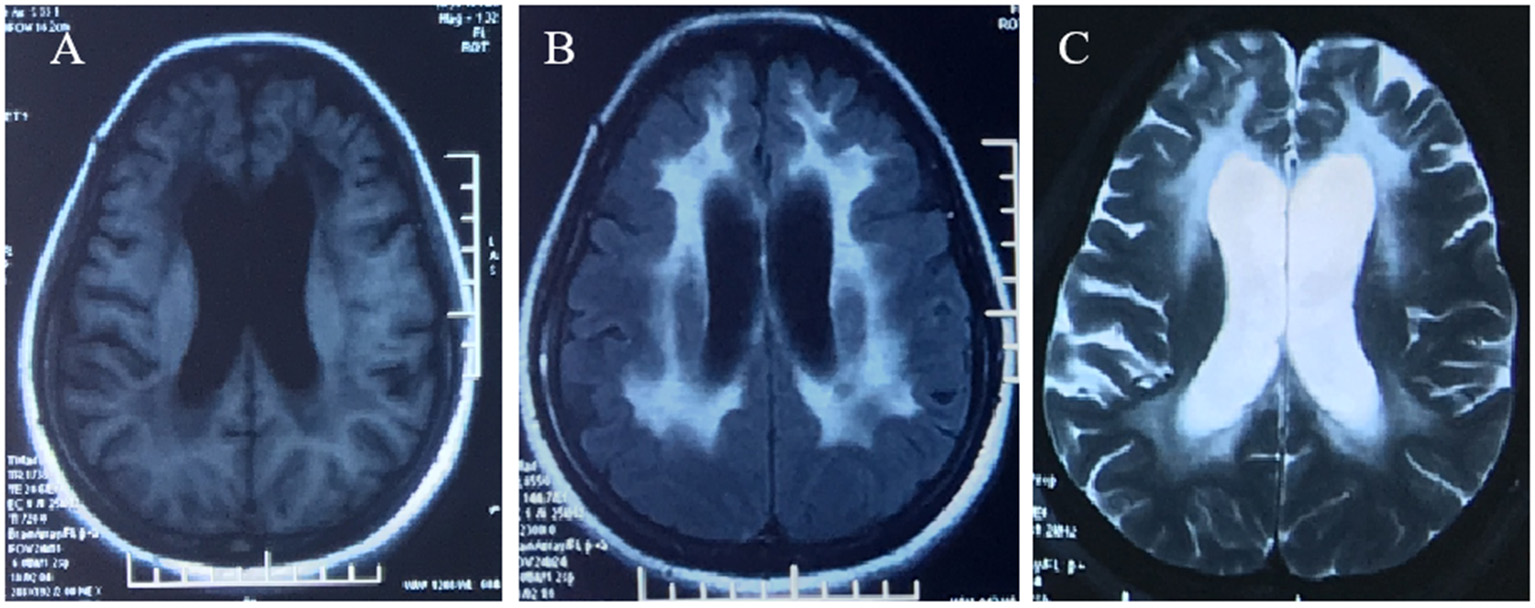

A 42-year-old woman suffered from progressive memory loss in the first half of the year before our evaluation. She gave birth at full term via normal vaginal delivery without distress and dysmorphic features and grew normally. Half a year ago, she began to lose her memory, being unable to recall what just happened, and progressively aggravated. There was no known antecedent brain injury, and her medical history was not obvious. Her father died of liver cancer, and her sister who suffered from unexplained dementia finally died at the age of 40 years. She had two children, a boy and a girl, both of whom were in good health. Neurological examination displayed remarkable symptoms in reaction dullness and memory loss, as well as horizontal nystagmus. The motor system examination revealed that her muscle strength was normal (Grade 5) and her movements were coordinated. The results of the sense system examination were normal. Tendon reflexes of upper and lower extremities markedly decreased without lateralization. She graduated from junior high school with a score of 8 on the Montreal Cognitive Assessment (MoCA) and 15 on the Mini-Mental State Examination (MMSE). She was diagnosed with moderate cognitive impairment. Adult-onset, chronic progress, and high-level brain function were affected, mainly manifested as cognitive impairment. Moreover, the peripheral nerve might be involved according to the examination of weakened tendon reflexes. Neuroradiologically, brain magnetic resonance imaging (MRI) scans demonstrated diffuse and symmetrical abnormal signals in the cerebral white matter, especially around the top of the lateral ventricle (Figure 1). The activity of ARSA measured in white blood cells was 14.13 nmol/17h/mg, which was significantly lower than the normal value (>58 nmol/17h/mg). Nerve conduction studies showed that the evidence of polyneuropathy was superimposed upon diffuse, uniform demyelinating, and sensorimotor polyneuropathy. Electromyography (EMG) was remarkable for fibrillations and positive waves were limited to the right musculi abductor pollicis brevis. Genetic analysis indicated that there were two heterozygous mutations in the exon region of the ARSA gene: (1) NM_000487: c.[185_186dupCA], p.(Asp63GlnfsTer18). A duplication of CA nucleotides located in exon 1 at c.185_186 resulted in a frameshift mutation (Figure 2). (2) NM_000487: c.[154G>T], p.(Gly172Cys), rs74315271. A missense mutation of ARSA in exon 3 resulted in guanine being changed into thymine at nucleotide 154 (Figure 2), and amino acid Gly being replaced by Cys (Figures 3A,B). C.[185_186dupCA], p.(Asp63GlnfsTer18) was previously reported as a pathogenic mutation in the ARSA gene associated with MLD, but c.[154G>T], p.(Gly172Cys) was a novel mutation, which has not been reported in exome analysis. To predict whether this novel mutation is deleterious or not, the function of protein was predicted. Rare Exome Variant Ensemble Learner (REVEL), Polymorphism Phenotyping v2 (PolyPhen-2), MutationTaster, and Genomic Evolutionary Rate Profiling+ (GERP+) all indicated that the mutation was deleterious. She was eventually diagnosed with adult-onset MLD. Family genetic analysis revealed that her mother and son were identified to carry the heterozygous mutation of c.[185_186dupCA], p.(Asp63GlnfsTer18), and her daughter was the carrier of the heterozygous mutation of c.[154G>T], p.(Gly172Cys) (Figure 2). Unfortunately, this study could not collect blood samples from her father and sister due to the fact that they had passed away. The mode of inheritance of MLD is autosomal recessive, and a genetic family tree (Figure 3C) had been made. The patient was discharged soon after admission. At present, the patient is currently under follow-up.

Figure 1

Brain MRI demonstrated diffuse, symmetrical abnormal signal in the bilateral cerebral white matter, which was low signal in T1WI (A), high signal in FLAIR (B), and high signal in T2WI (C).